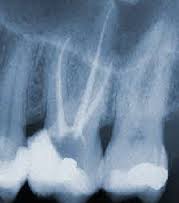

Unutar krune i korena nalazi se zubni nerv koji može oboleti usled pojave dubokog karijesa ili povrede zuba. Ovaj postupak predstavlja stomatološki tretman u kome se oboleli živac odstrani, a njegova neposredna okolina očisti od prisutne infekcije. Na kraju ovog tretmana potrebno je zub napuniti određenim materijalom.

Lečenje kanala korena